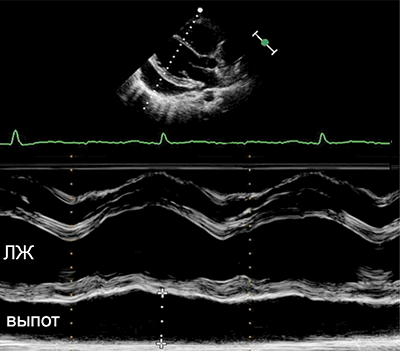

• Выпот (>15–35 мл), сепарация эпикарда и перикарда >1 мм в диастолу.

• Величина выпота: малый (сепарация • Утолщение (>3–4 мм) и кальцификация перикарда (констриктивный перикардит).

• Эхокардиография: колебания сердца, выраженный выпот (>20 мм), диастолический коллапс камер сердца, аномальное движение МЖП, > вариабельности митрального потока (>25%) на вдохе.

• Выраженная сепарация эпикарда и перикарда >20 мм в диастолу на эхокардиограмме.